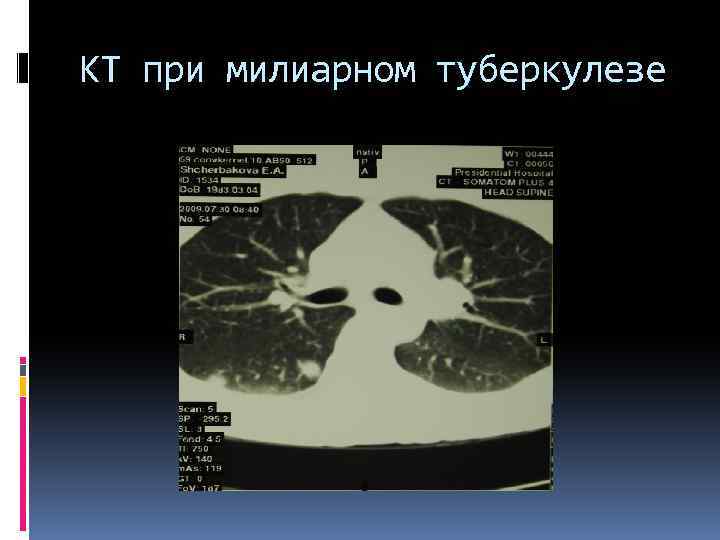

Компьютерная томография На КТ определяются множественные, мелкие (1— 2 мм), однотипные очажки, густо и равномерно расположенные по всем полям с обеих сторон. Очаги, четко очерченные, не сливаются. Интенсивность их средняя. Из-за большого количества очагов не виден сосудистый рисунок легкого. При обратном развитии болезни очаги могут полностью рассосаться или же кальцинироваться. Количество кальцинированных очагов меньше, чем в период высыпания, так как частично очаговые изменения рассасываются. Располагаются очаговые высыпания симметрично, как правило, во всех полях легких, на фоне пневмосклероза. Сохраняются на всю жизнь. При прогрессировании процесса, вследствие трофических изменений в легких, появляется распад легочной ткани в виде характерных тонкостенных каверн. Обычно каверны множественны, округлы, одинаковы по форме и по размерам. Поэтому они названы «штампованными» . Иногда они расположены цепочкой, нередко симметрично в обоих легких. В таких случаях их называют системой каверн.

КТ при милиарном туберкулезе